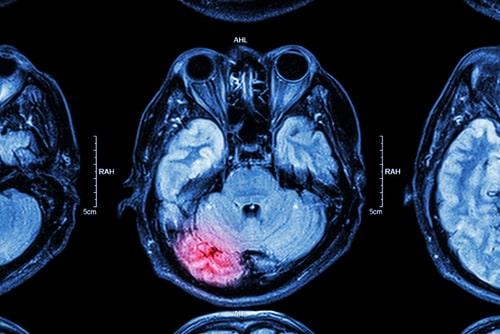

IL injury lawyerIn recent years, there has been increasing awareness of the dangers that professional athletes face due to the high risk of serious brain injury. The risk is heightened if you play a sport with a higher chance of repeated trauma to the head, like in hockey, wrestling, and football for example. The repeated hits to the head suffered by someone who has been playing a particular sport professionally for several years can lead to the development of what is known as chronic traumatic encephalopathy (CTE), which can result in severe disability. If a loved one suffered brain trauma that developed into CTE, speak with a knowledgeable Naperville, IL personal injury attorney with experience in similar cases to understand how to move forward.

CTE is linked to repeated head trauma, and professional athletes are among the groups with the highest risk of developing it. This disease often gets worse over time and can even lead to dementia. There are four main stages of CTE, with the symptoms associated with these stages generally appearing between eight and ten years after the repetitive brain trauma. The stages are: